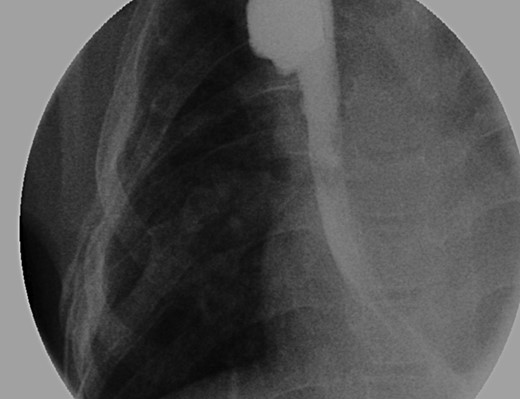

With the distal colon graft in place, as well as the distal esophageal segment, we recommended a combined procedure with graft removal and growth induction given the 8.2-cm gap (Fig. 1A and B). A thoracoabdominal incision was made and the colonic conduit was dissected away from the diaphragm; extensively mobilized from the left lateral segment of the liver and lung; and, transected from its anastomosis with the stomach. The stomach was then repaired in two layers. Traction sutures, using 4.0 prolene sutures, were then placed in the muscular layer of the distal esophageal segment and brought out onto the chest wall.

(A) Lateral view during her initial fluoroscopic examination illustrating a small, distal (lower) esophageal remnant present in situ (Black arrows). Contrast was injected through her existing gastrostomy tube. (B) Anterior–posterior (AP) view during initial fluoroscopic examination illustrating an aperistaltic, native colonic interposition in situ with significant dilatation.